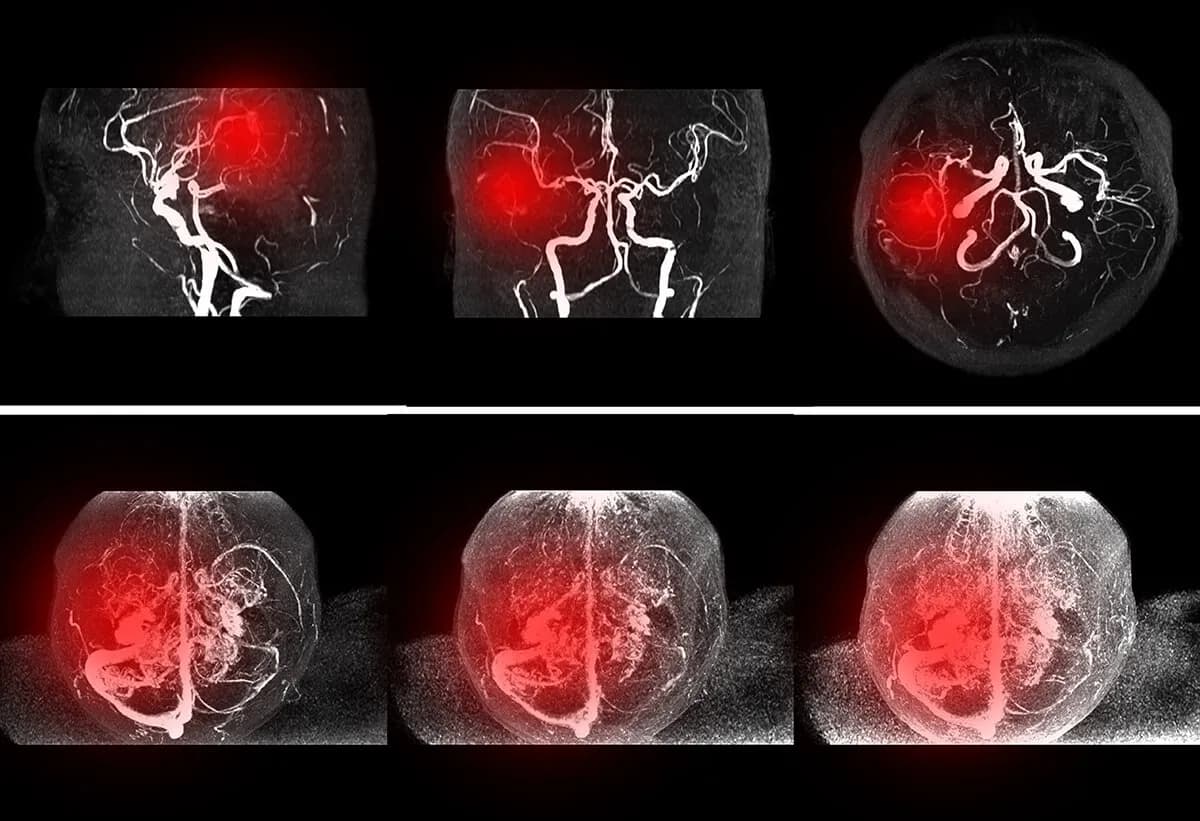

Diagnostyka bólu tętnicy szyjnej jest kluczowym krokiem w ocenie stanu zdrowia pacjenta. Lekarze mogą zlecić szereg testów diagnostycznych, aby określić przyczynę bólu oraz ocenić stan tętnic szyjnych. Jednym z najczęściej wykonywanych badań jest ultrasonografia Dopplera, która pozwala na ocenę przepływu krwi w tętnicach oraz wykrycie ewentualnych zwężeń lub zatorów. To nieinwazyjne badanie jest szybkie i skuteczne, co czyni je pierwszym krokiem w diagnostyce.

Inne testy diagnostyczne mogą obejmować angiografię, która wykorzystuje kontrast do wizualizacji naczyń krwionośnych, oraz rezonans magnetyczny (MRI), który dostarcza szczegółowych obrazów tętnic i otaczających tkanek. W niektórych przypadkach lekarz może zlecić także tomografię komputerową (CT), aby uzyskać dokładniejsze informacje o stanie tętnic szyjnych. Wybór odpowiednich badań zależy od objawów pacjenta oraz podejrzenia konkretnego schorzenia.